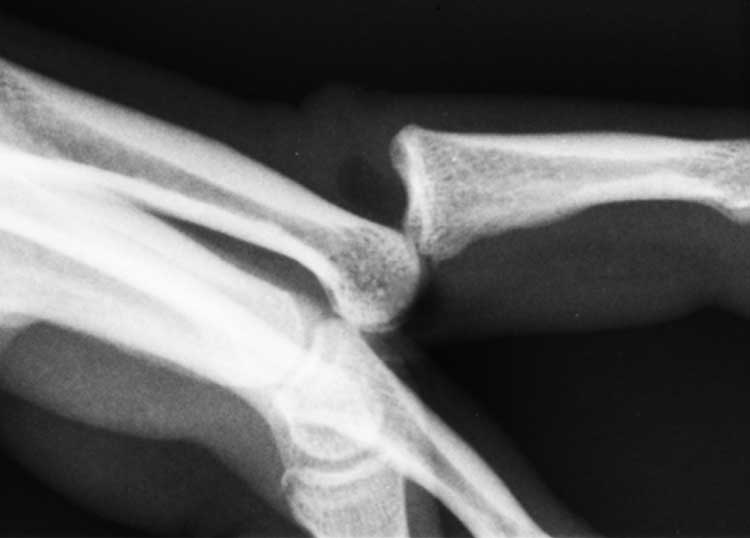

Para controlar las grietas y atraparlas con la resonancia magnética, los investigadores conectaron a los dedos de Fryer tubos que lentamente estiran lo suficiente para inducir un pop.

Con sólo un sujeto (a pesar de que, ofreció los 10 dedos) y no hay grabación de sonido real en el MRI, el estudio está lejos de un final concluyente para el debate. Pero en cada crackeo de prueba, fue vista la formación de una cavidad en el momento exacto en que el sonido se escuchó. Además, Kawchuk y sus colegas no observaron ningún colapso de la cavidad – por lo menos no en el período inmediatamente posterior al tronarse los nudillos – por lo que no se ve cómo podría provocar el ruido.